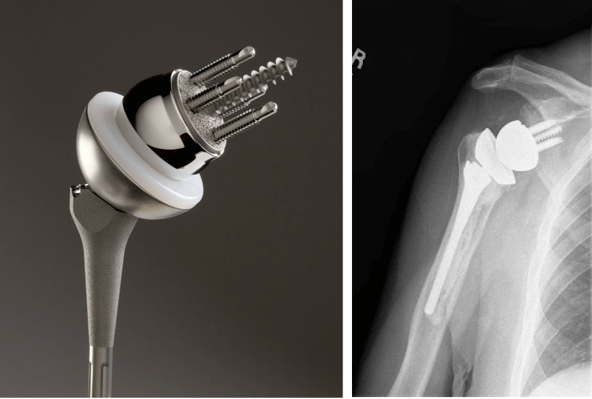

Имплантаты на ножке по своему строению могут быть анатомическими и обратными. Анатомический состоит из трех частей: головка, ножка и впадина. Назван так, поскольку полностью повторяет структуру человеческого плеча и по биомеханике, и по форме.

Установка такого протеза возможна только в том случае, если вращательная манжета не повреждена. При замене используется продукция таких мировых производителей как DePuy, Zimmer, Smith&Nephew, Biomet, Aesculap — B. Braun.

Обратный или реверсивный используется, когда вращательная манжета не функционирует и нарушена стабильность. Тогда головка крепится к суставной впадине (гленоидальному компоненту), а вогнутый имплантат впадины на ножке фиксируется на плечевой кости.

Ревизионное эндопротезирование в случае обширного поражения тканей, замены эндопротеза или сильного разрушения кости требует специального имплантата, который частично компенсировал бы функциональную недостаточность мышц. Например, Delta XTEND производства компании DePuy. Центр ротации у него смещен вниз и кнаружи, что увеличивает диапазон движений, сохраняя при этом стабильность сустава.